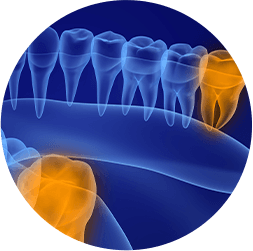

wisdom teeth

Is someone in your life dealing with erupting wisdom teeth? This situation is common for people in their late teens and for young adults. Tooth damage, discomfort, infections and even cysts can all be indicators that it is time to call our office for an appointment for wisdom teeth removal. Contact our team today.